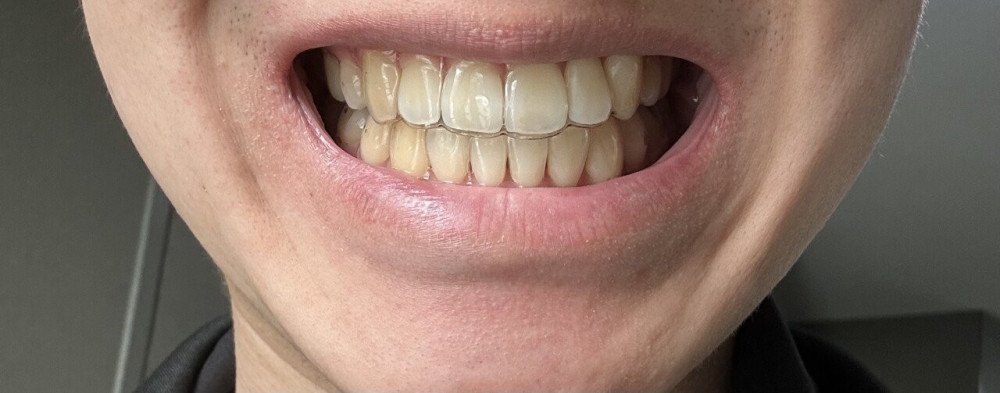

2년 7개월간의 교정이 끝난 펨코인